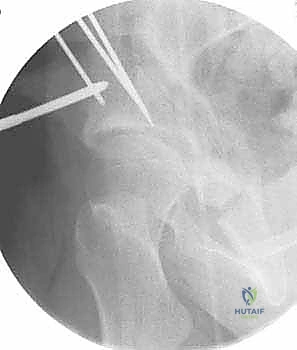

تُعد هذه الجراحة سيمفونية من الدقة الجراحية. تستغرق العملية عادة من 2 إلى 4 ساعات، وتتم تحت التخدير العام أو النصفي المتقدم مع التحكم في الألم (Epidural). إليك تفصيل للخطوات الميكانيكية الدقيقة التي ينفذها الأستاذ الدكتور محمد هطيف باحترافية عالية:

2. سلسلة قطع العظام (The 5 Osteotomies)

يكمن سر نجاح جراحة PAO في إجراء خمسة قطوع عظمية منفصلة حول الحُق، لتحريره بالكامل عن باقي الحوض، مع ترك العمود الخلفي سليماً كدعامة أساسية.